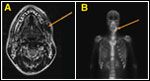

The radiographic findings in ONJ are variable. Less advanced ONJ or smaller areas of exposed bone (< 1 cm) is often undetectable on panoramic radiographs but shows faint signals or evidence of bony destruction on bone and CT/MRI scans. Progressive or advanced ONJ shows increased uptake on bone scans and "mottled bone" or areas of lytic changes on CT/MRI scans and panoramic radiographs (Figures 2 and 3).

FIGURE 3

Advanced Osteonecrosis of the Jaw